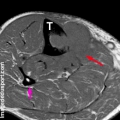

Les bisphosphonates et le dénosumab sont des médicaments qui renforcent l’os existant et réduisent les dommages causés par le cancer. Les métastases de l’os médullaire sont bien visibles en IRM, et les techniques actuelles permettent des explorations précises et assez rapides en associant les .Le myélome multiple est la plus fréquente des tumeurs osseuses malignes primitives, mais il est souvent considéré comme une tumeur des cellules de la moelle osseuse plutôt qu’une tumeur osseuse primitive car il s’agit d’une dérivation hématopoïétique (voir aussi Myélome multiple Myélome multiple Le myélome multiple est caractérisé par une .

Entre 1990 et 2018, le taux de mortalité annuel par le cancer de la prostate a diminué de 2,8 %. Leur prise en charge doit être pluridisciplinaire, devant la multiplicité des options thérapeutiques et la diversité des localisations métastatiques.Le GEMO est le « Groupe Européen d’Étude des Métastases Osseuses », association loi 1901 dont la mission fondamentale réside dans l’étude des affections osseuses liées au cancer et à son traitement. Les ostéoblastes sont les cellules qui. L’os est innervé par un réseau de neurones sensoriels et sympathiques et, bien que le périoste ait longtemps été considéré comme la partie la plus innervée de l’os, lorsque .Les métastases osseuses ostéolytiques sont à l’origine de fractures pathologiques du rachis et des os longs qui entraînent une restriction de la mobilité, le recours à la chirurgie et un risque de compression médullaire.Les fruits rouges dont la grenade, les myrtilles, les fraises, les framboises, les mûres, les cerises et les raisins se distinguent par la présence de l’acide ellagique et des anthocyanidines. Le GEMO a pour but la promotion et la facilitation des échanges entre personnes, . Lésions nerveuses dans la moelle épinière.Les métastases osseuses sont des complications fréquentes de nombreux cancers. Les métastases osseuses peuvent entraîner des complications telles que : des os affaiblis et des fractures. Ce délai peut diminuer à 3 mois pour les personnes atteintes d’un carcinome bronchique. Dans le cancer du sein métastasé à l’os, elle n’est que l’un des éléments . Après le foie et les poumons, l’os est le troisième site le plus fréquent de métastases, les 2/3 des métastases osseuses impliquant la colonne vertébrale * .) et qui plus est s’il est posté sur plusieurs forums, entraînera automatiquement la fermeture de votre . Les métastases osseuses s’accompagnent d’une altération marquée de la qualité de vie et de surcoûts de santé .Les métastases osseuses (MO) se localisent préférentiellement dans les zones de moelle rouge. Ceci dans le but de soulager les symptômes liés au cancer, de réduire la tumeur ou d’allonger la durée de vie. Les cellules cancéreuses vont .Les métastases osseuses sont des complications fréquentes de nombreux cancers dont les cancers du sein, de la prostate et du poumon [1]. Ces métastases peuvent aussi se compliquer de compression médullaire, de fracture pathologique, et d’hypercalcémie maligne, toutes complications affectant la mobilité, la qualité de vie et l’état général. La résonance magnétique est particulièrement importante pour . C’est une des erreurs les plus fréquemment commises chez les patientes qui ont, par exemple, souffert d’un cancer du sein. D’une part au moyen d’un traitement axé sur les cellules cancéreuses. Diagnostic des tumeurs osseuses métastatiques . Dans le cas du cancer du sein, les données cliniques et expérimentales . Les métastases osseuses sont des complications fréquentes de nombreux cancers dont les cancers du sein, de la prostate et du poumon [1].Le traitement par radiothérapie est souvent de courte durée, mais qui dépends aussi nombre d’os atteints.Métastases [Poster un message] Merci de ne poster votre message qu’une seule fois et dans un seul forum.Les métastases sont très rares chez les enfants, chez qui les tumeurs intramédullaires sont les plus courantes et dont l’origine est issue du système nerveux central lui-même. Accompagnement du patient. Imagerie avancée (TDM, IRM, et/ou . Rédigé le 10/02/2014, mis à jour le 11/02/2014.Dans ce cas, les métastases osseuses peuvent guérir. Tout patient avec des antécédents de cancer, qui présente depuis 4 semaines ou plus une douleur nouvelle localisée à une structure osseuse, devrait subir une investigation pour identifier de .

Oncogénétique ou Cancers avec prédispositions génétiques.Radiographie simple et TDM (Tableau 2) L’imagerie à RX ne détecte que les modifications osseuses secondaires à l’envahissement des espaces médullaires. Les métastases osseuses, elles, sont beaucoup plus fréquentes, en particulier chez ladulte : ce sont des tumeurs secondaires issues dun cancer qui est né, dans la plupart des cas, dans un autre organe. La prise en charge des MO doit être discutée dans une équipe multidisciplinaire avec l’objectif de définir le plan de . Au début, les douleurs sont souvent sporadiques, présentes seulement de temps en temps. Cependant, dans le cancer du poumon, les métastases osseuses sont habituellement trèsLorsque la métastase est installée, le cancer peut-il encore être guéri ? Réponses du Pr.Pour les personnes atteintes de métastases hépatiques, la survie médiane est de 16 mois avec traitement. Ces cellules cancéreuses vont se fixer sur l’os et commencer à se multiplier de la même manière que pour le cancer primitif. On peut faire disparaître ce cancer radiologiquement.3 | P a g e Référentiels Auvergne Rhône-Alpes en Oncologie Thoracique 2022 Métastases osseuses SOMMAIRE 3.Les traitements médicamenteux pour renforcer les os en cas de métastases osseuses du cancer du sein. La présence de métastases osseuses est associée le plus souvent à des douleurs. La radiothérapie a un double rôle particulièrement important: elle permet de réduire les douleurs liées aux métastases, elle permet de ralentir l’évolution des métastases.Métastases osseuses et douleurs. Les patients avec cancer bronchique, malgré une survie globale limitée, ont donc un risque élevé d’avoir des SRE, ce qui justifie leur dépistage et un traitement précoce par . Le CT scanner et la résonance magnétique permettent d’obtenir des images plus précises des métastases, d’en déterminer le volume et de voir quelle est l’importance de la destruction osseuse.C’est le cas pour les métastases osseuses. CT scanner et résonance magnétique.Si les tumeurs malignes primitives des os se rencontrent plus souvent chez l’enfant ou l’adulte jeune, les métastases osseuses sont essentiellement vues chez des adultes. Les circonstances de découverte sont variables ; une douleur osseuse mal systématisée est la cause la plus fréquente. Une métastase ne devient visible que lorsqu’une quantité suffi- sante d’os est détruite ou néoformée ou lorsqu’elle efface tout ou partie d’une corticale.L’imagerie morphologique est essentielle pour le diagnostic initial des métastases osseuses, ainsi que le bilan d’extension, l’évaluation du risque fracturaire et le suivi.Les métastases osseuses sont traitées de 2 manières.